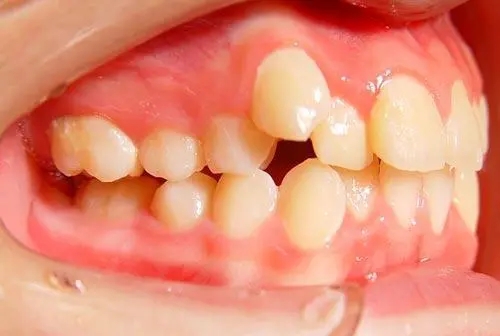

5.牙齿排列不齐

牙齿不齐,不仅拉低颜值,还很容易塞牙,多出现在全部恒牙换好之后。如任其自然发展,容易造成塞牙,并会有其它一系列的口腔问题。